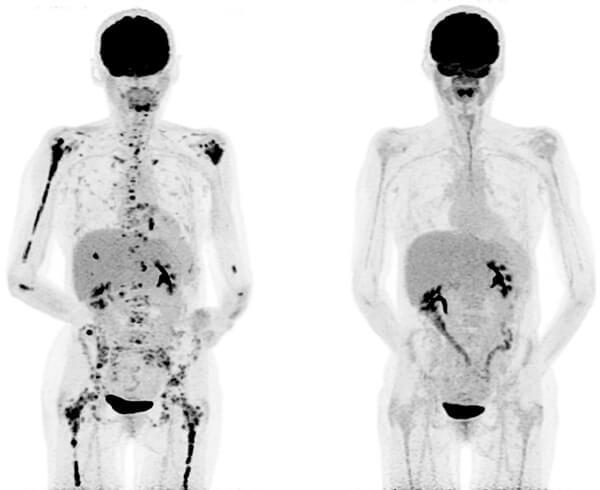

Two side-by-side PET scans of an adult body with multiple myeloma. The scans are mostly light grey; in the left scan, there are black areas spread throughout the shoulders, right arms, and throughout the lower body. On the right scan, after the BCMA-targeted CAR T cell treatment, there are approximately 80% less black areas; those that remain are mainly located in the midsection.

Before (left) and after (right) PET scans of a patient with multiple myeloma treated with BCMA-targeted CAR T cells.